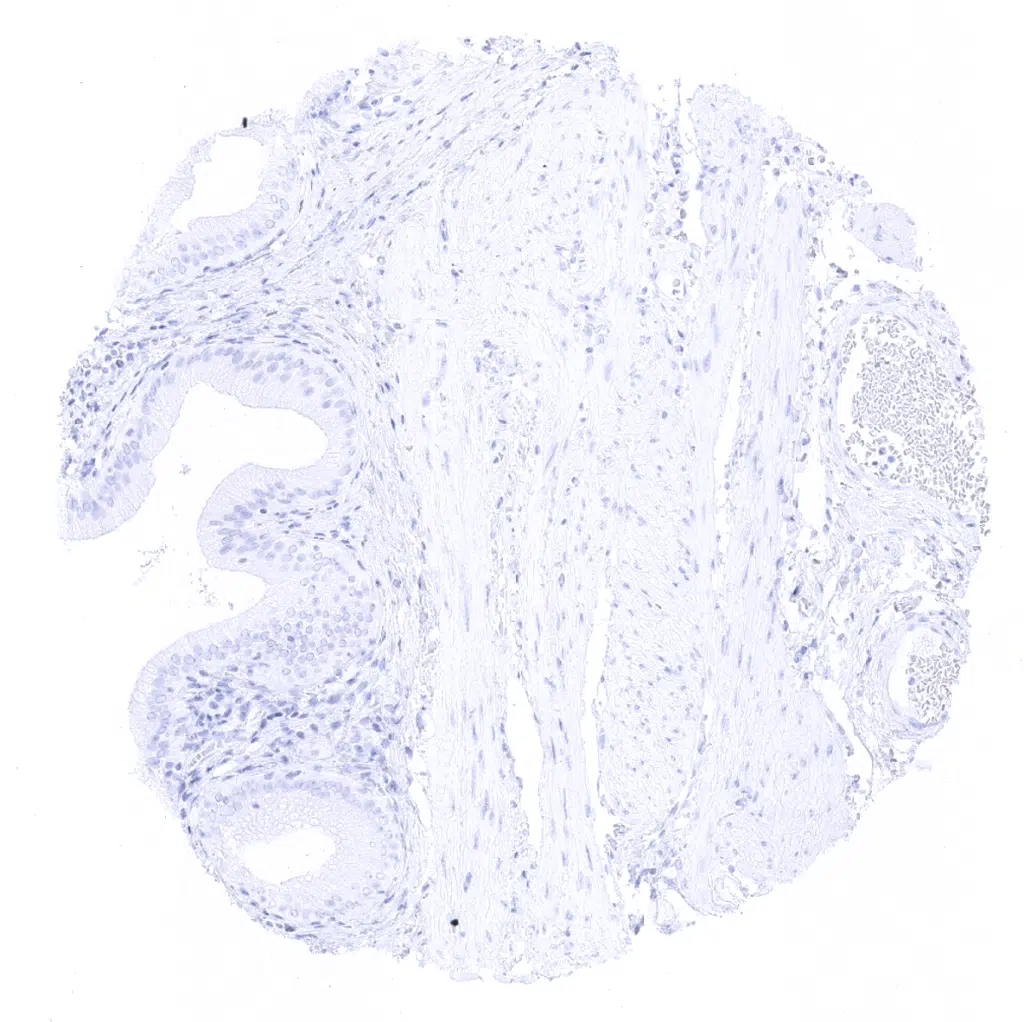

Ectocervix